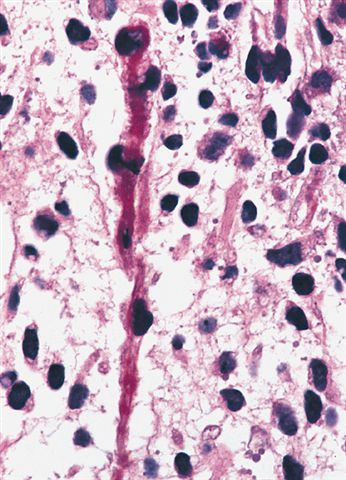

Microscopic (histologic) description

- Composed of primitive mesenchymal cells that show variable degrees of skeletal muscle differentiation

- They are moderately cellular but in the typical pattern often contain both hypocellularity and hypercellular areas with a loose, myxoid stroma

- Perivascular condensations of tumor cells in the less cellular regions are common

- Sheets of small, stellate, spindled or round cells with scant or deeply eosinophilic cytoplasm and eccentric, small oval nuclei with a light chromatin pattern and inconspicuous nucleoli

- Can occasionally identify tumor cells that contain generous amounts of eosinophilic cytoplasm, a feature of rhabdomyoblastic differentiation (so called strap cells)

- These may become more prominent with chemotherapy (chemotherapeutic induced cytodifferentiation)

- May have cells with elongated tails of cytoplasm (tadpole cells)

- If densely cellular, may resemble solid alveolar rhabdomyosarcoma (Am J Clin Pathol 2013;140:82)

- Cells are undifferentiated, round or spindled with minimal cytoplasm, frequent mitotic figures

- Deeper layers of the tumor are typically less cellular but overall conform to the histology of embryonal rhabdomyosarcoma (ERMS) with variation by region

Microscopic (histologic) images

Contributed by Erdener Özer, M.D., Ph.D. and Mark R. Wick, M.D.

Contributed by Carolina Martinez Ciarpaglini, M.D., Ph.D. (Case #276) - tonsillar mass

AFIP images - anaplastic rhabdomyosarcoma

AFIP images - botryoid variant